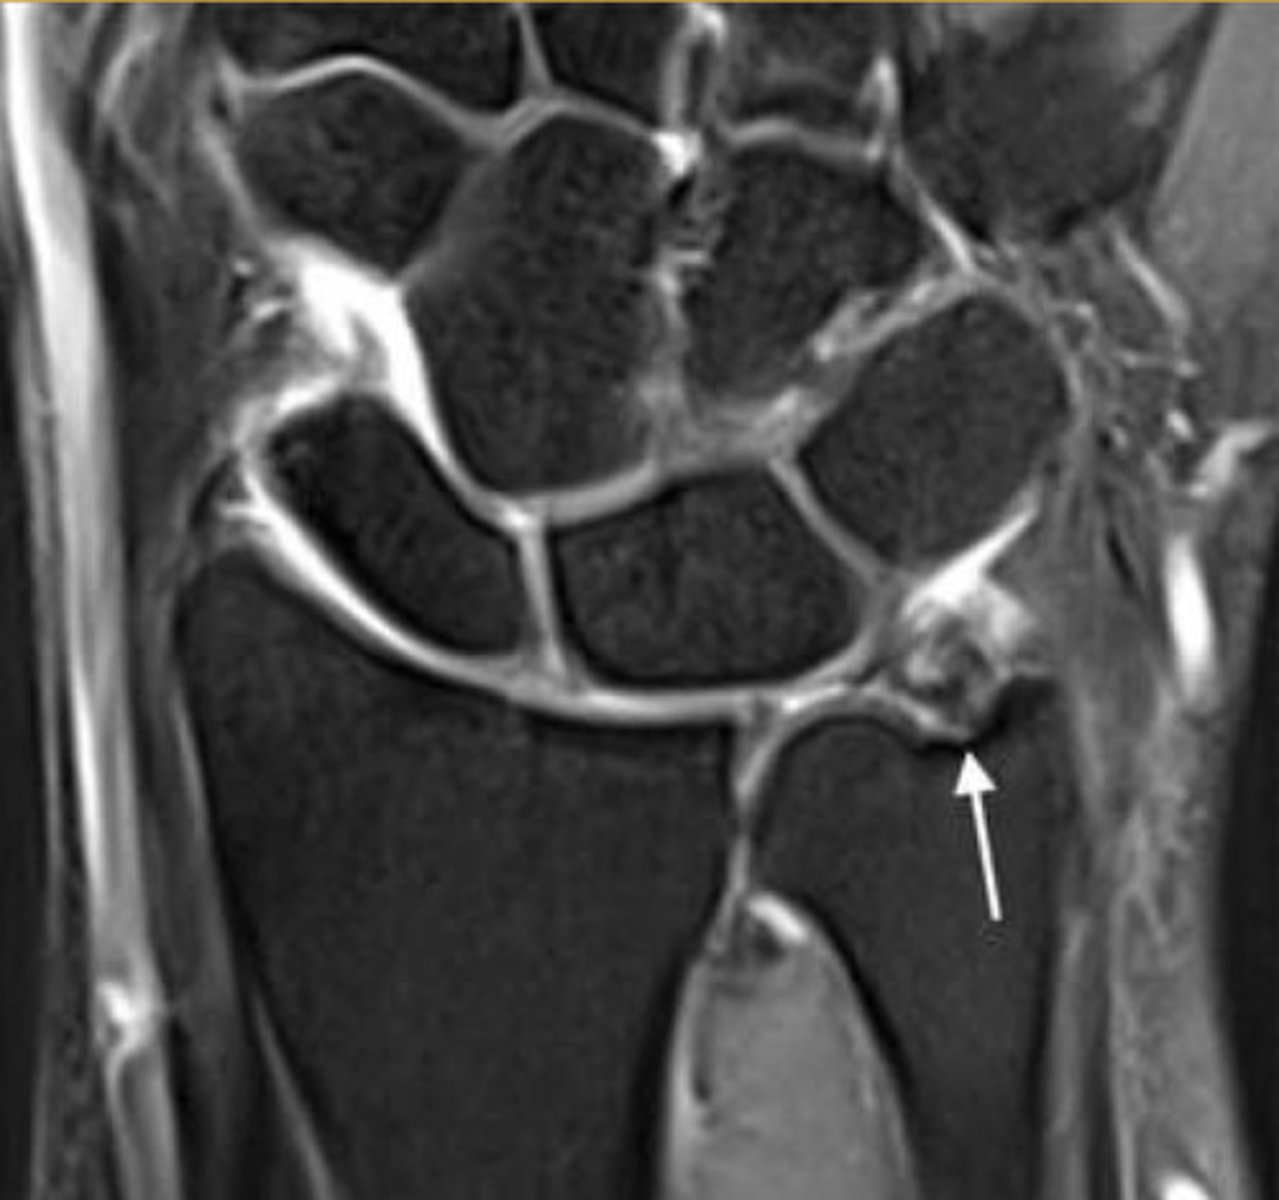

Positive Ulnar Variance

Relative lengthening of the ulna compared to the radius

Measured by comparing the distal ends of each bone

Clinical significance of positive ulnar variance

May lead to ulnar abutment (impaction) of the lunate and TFCC (triangular fibrocartilage complex) degeneration

May be associated with triangular fibrocartilage tear